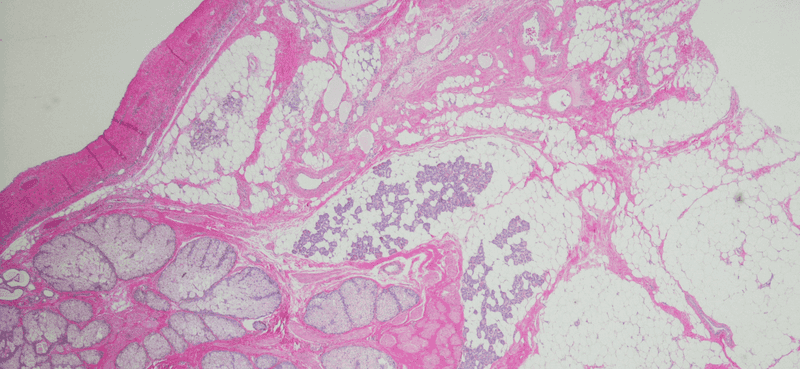

Sichtbar werden bei der zystischen Akne meistens Mitesser und gerötete Pickel (Pusteln), die besonders schmerzhaft sind. Der Grund dafür: Die oberflächlich Symptome entstehen aus Zysten, die sich tiefer in der Haut bilden. Dort liegen Infektionen, die sich zuerst zu den Zysten bilden und anschließend langsam in die oberen Hautschichten hervortreten.

Deshalb sind die Symptome der zystischen Akne häufig schon schmerzhaft, bevor sie sichtbar werden und können auch ohne Berührungen für Schmerzen oder Spannung im Gesicht sorgen.

Für sie bedeutet diese Veränderung eine Überproduktion – die Talgdrüsen füllen sich, schwellen an, verhärten sich und können in der Folge den überschüssigen Talg nicht an die Hautoberfläche absondern. Sie brechen unter der Haut auf und verursachen akute Entzündungen, die sich zu Zysten entwickeln können. Wahrscheinlich nimmst Du diese, spätestens wenn sie an der Hautoberfläche sichtbar werden, als besonders große und unangenehme Pickel wahr.